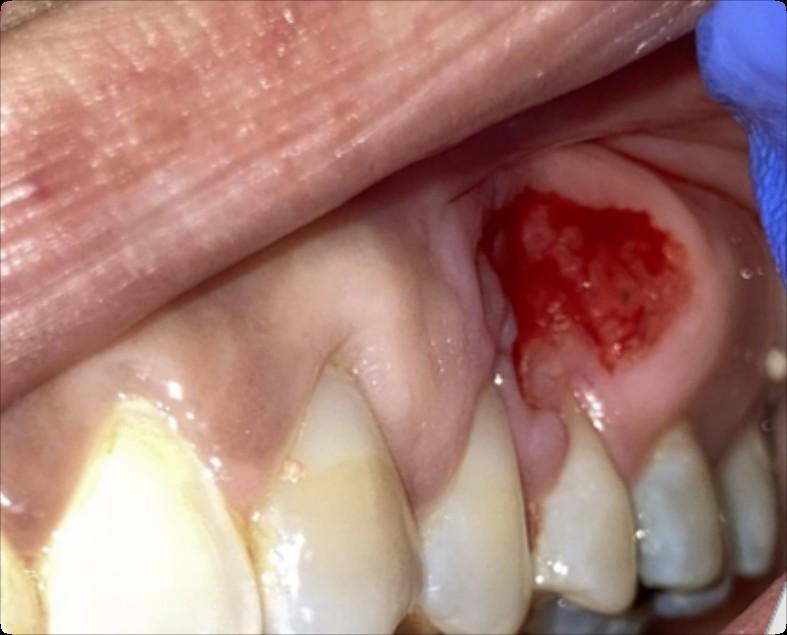

Osteonecrosis of the Jaw

MRONJ: Medication Related Osteonecrosis of the Jaw

• Rare oral side effect called osteonecrosis of the jaw that is associated with certain medications, bone-modifying agents.

• Osteonecrosis of the jaw is a condition where small area(s) of the jawbone have difficulty healing and the bone starts to breakdown and die.

What are the signs of MRONJ?

• The hallmarks of ONJ are exposed bone or gum/mucosa/tissue wounds that heal very slowly or do not heal at all for eight weeks or more after an injury to the mouth.

• Some patients report that this begins with a feeling of “roughness” on the gum tissue. If these open wounds become infected, there may be pus or swelling in the adjacent gum tissue.

• Many times, this condition is painless in the beginning, and patients only experience pain after the exposed bone becomes infected.

How is MRONJ treated?

• Education

• Careful oral hygiene

• Conservative interventions

• Avoid surgical intervention, if possible

• PATIENCE!